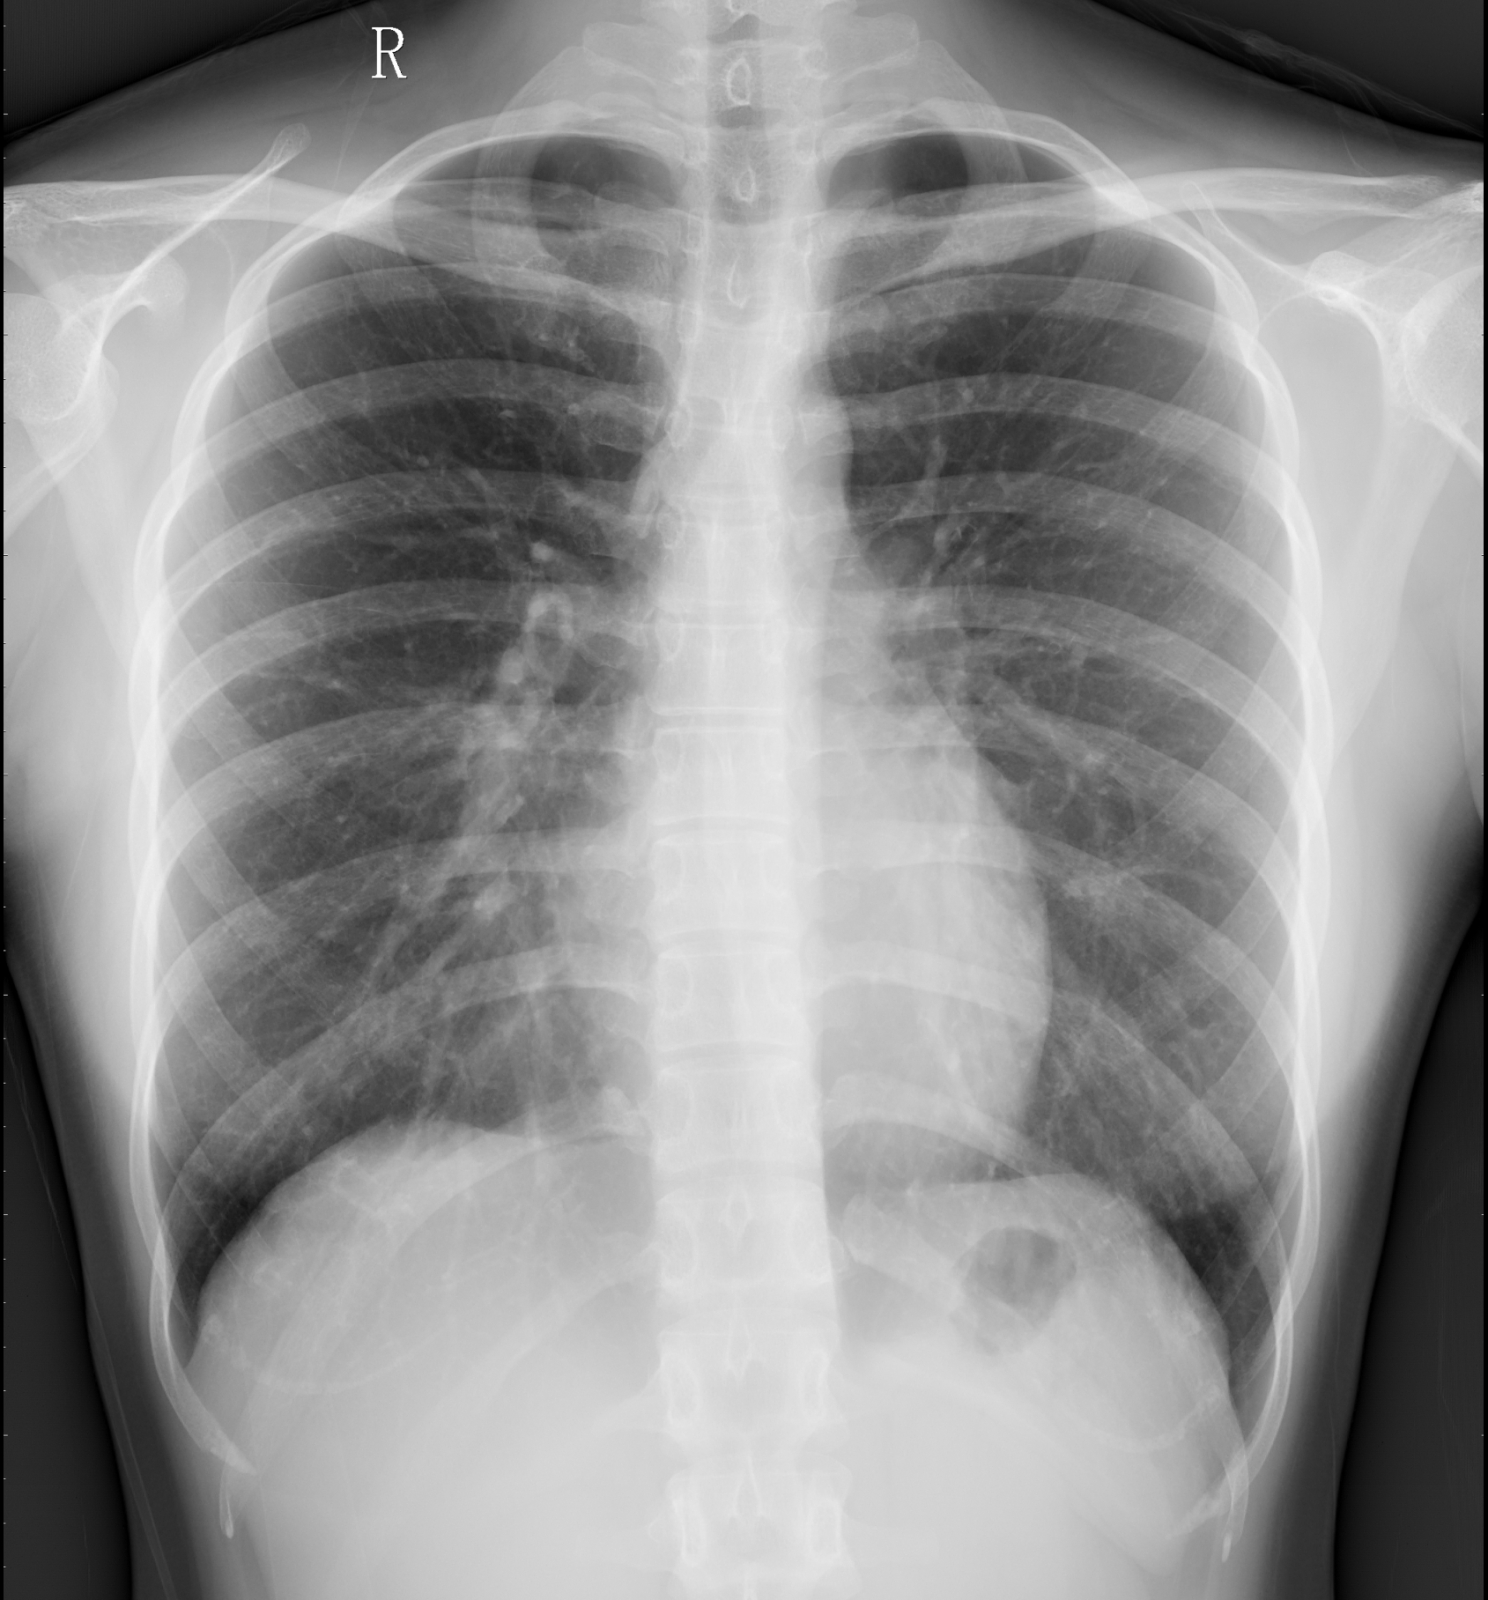

X线

X线检查利用不同组织对X线吸收差异成像,形成明暗对比影像。优点:高空间分辨率、低曝光、成像快、操作简便且经济。缺点:组织重叠易漏诊,密度相近的组织和病变难以分辨。

(胸部正位片影像)

2)胸部:粗看X线,细看CT。

X线摄影:快速筛查的“初诊医生”

胸部检查的初步阶段,X线摄影以其便捷、经济、辐射量相对较低的特点,成为了首选的筛查工具。它如同一位经验丰富的“初诊医生”,能够迅速捕捉并呈现胸部的大致轮廓与关键信息。通过X线片,医生可以直观地观察到双肺纹理的清晰度与分布状态,初步判断是否存在炎症、水肿或纤维化等异常;同时,也能对心脏的大小、形态进行粗略评估,以及筛查肋骨是否存在畸形或骨折等骨骼问题。